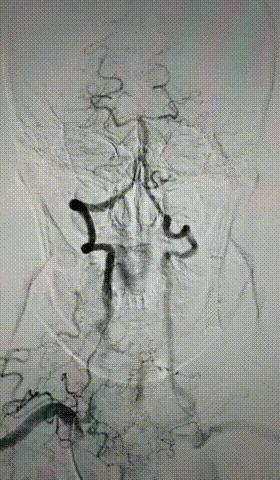

脑动脉盗血综合征(steal syndrome)

脑动脉盗血综合征是指各种原因引起的主动脉弓及其附近大动脉血管严重狭窄和闭塞,狭窄远端的动脉内压力明显下降,邻近的脑动脉血流逆流至压力较低的动脉,以代偿其供血,导致被盗血的脑动脉供血显著减少,引起脑组织缺血,出现相应的临床症状体征。

指一侧锁骨下动脉在其近心端发出椎动脉前狭窄或闭塞时,因“虹吸作用”颅内血流经患侧椎动脉逆流进入锁骨下动脉代偿患侧上肢的血液,而导致颅内缺血的症状。动脉粥样硬化是其最常见原因,其次为动脉炎。